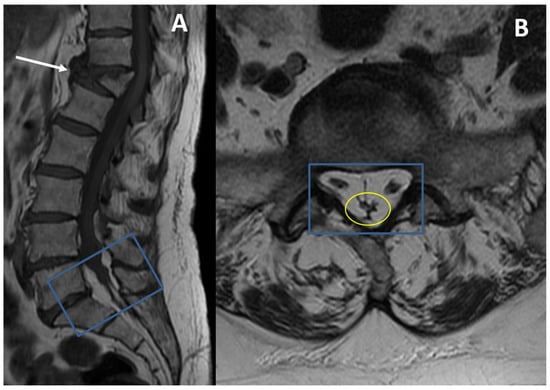

- Spinnato, P.; Barakat, M.; Lotrecchiano, L.; Giusti, D.; Filonzi, G.; Spinelli, D.; Pipola, V.; Moio, A.; Tetta, C.; Ponti, F. MRI Features and Clinical Significance of Spinal Epidural Lipomatosis: All You Should Know. Curr. Med. Imaging 2022, 18, 208–215. [Google Scholar] [CrossRef] [PubMed]

- Spinnato, P.; Lotrecchiano, L.; Ponti, F. “Y” sign in spinal epidural lipomatosis. Jt. Bone Spine 2020, 88, 105056. [Google Scholar] [CrossRef]

- Kuhn, M.J.; Youssef, H.T.; Swan, T.L.; Swenson, L.C. Lumbar epidural lipomatosis: The “Y” sign of thecal sac compression. Comput. Med. Imaging Graph. 1994, 18, 367–372. [Google Scholar] [CrossRef]

- Geers, C.; Lecouvet, F.E.; Behets, C.; Malghem, J.; Cosnard, G.; Lengelé, B.G. Polygonal deformation of the dural sac in lumbar epidural lipomatosis: Anatomic explanation by the presence of meningovertebral ligaments. Am. J. Neuroradiol. 2003, 24, 1276–1282. [Google Scholar]